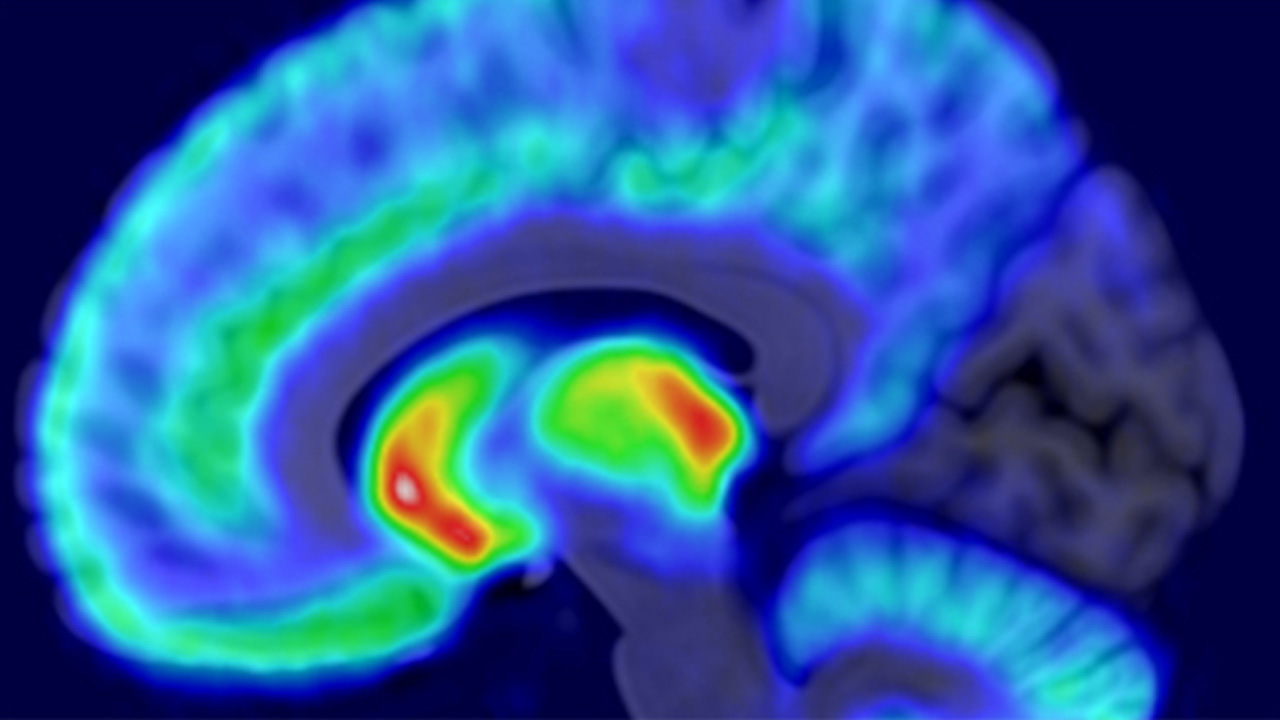

Cerebral Cortex -tiedelehdessä juuri julkaistu tutkimus tehtiin positroniemissiotomografian (PET) ja toiminnallisen magneettikuvantamisen (fMRI) avulla.

Tutkittavien verenkiertoon annosteltiin pieni määrä radioaktiivisia merkkiaineita, jotka sitoutuvat aivojen opioidi- ja dopamiinireseptoreihin. Merkkiaineiden hajoamista mitattiin PET-kameralla, minkä avulla voitiin määrittää reseptorien määrä aivoissa. Tämän jälkeen tutkittavien aivotoimintaa mitattiin fMRI-kokeessa, jossa he katselivat videoita, joissa ihmiset kokivat eri asteista kipua.